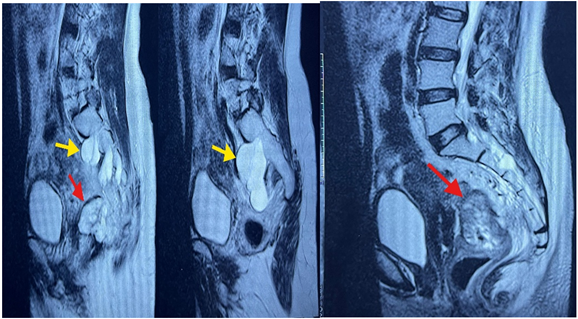

This was further evaluated with a lumbar MRI, which revealed multiple bilateral periradicular cysts involving the S1-S2, S2-S3, and S3-S4 foramina, with endopelvic extension and bony scalloping. The largest cyst, on the left at S1-S2, measured 41 x 28 x 71 mm, displacing the rectal fascia.

Figure 4: lumbar MRI image showing the Tarlov cysts (yellow arrow) and the rectal tumor (red arrow).